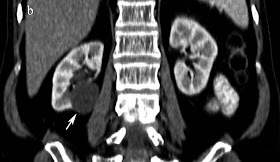

Axial CT of kidneys in a 29 year old male showing small exophytic fat attenuation lesion in the left kidney (arrow) suggestive of angiomyolipoma.

Zoomed picture of the above showed image better shows the lesion.

CT Scan: Well defined fat attenuation lesion as shown in our case. CT angiography may be helpful to identify the aneurysms which predict the fatal hemorrhage.